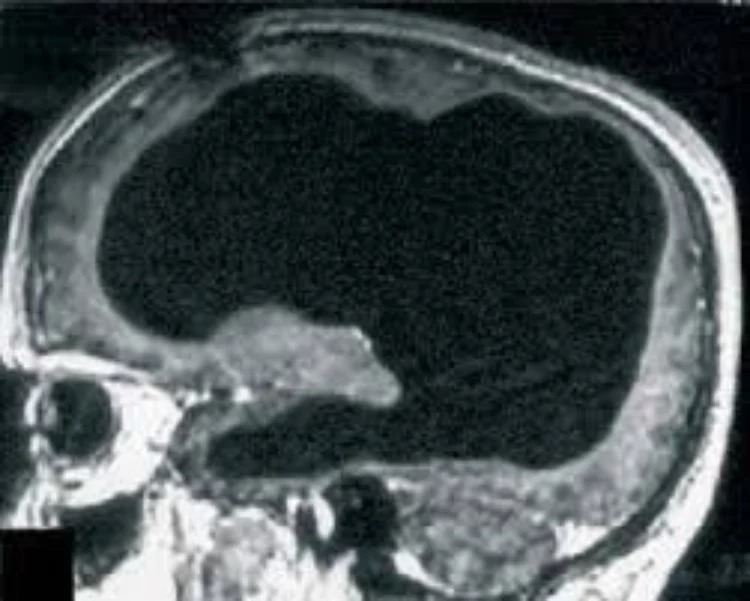

Những hình ảnh chụp CT và MRI từ Bệnh viện Marseille đã ghi lại một thực tế khó tin: phần lớn diện tích mô não được thay thế bằng chất lỏng dịch não tủy. Khi quan sát kỹ hơn qua hình ảnh MRI, thấy rõ rằng lớp mô còn lại cực kỳ mỏng manh chỉ bao phủ quanh thành hộp sọ mà thôi. Điều này càng làm nổi bật sự khác biệt to lớn so với cấu trúc bình thường của một bộ não khỏe mạnh.

Kết quả chụp CT và MRI tại Bệnh viện Marseille

Các xét nghiệm hình ảnh tại bệnh viện cho thấy phần lớn khối lượng mô não đã bị teo nhỏ nghiêm trọng. Quá trình chụp cho phép các chuyên gia xác định chính xác khu vực tổn thương cũng như mức độ thay thế bởi chất lỏng dịch não tủy nằm trong các khoang chứa không gian rộng lớn hơn rất nhiều so với bình thường.

Những khu vực não bị teo nhỏ và thay thế bởi dịch não tủy

Não bộ teo lại chỉ còn lớp mỏng bao quanh hộp sọ

Qua hình ảnh chi tiết, những vùng như vỏ đại não – nơi tập trung cao nhất các chức năng nhận thức – gần như bị tiêu biến hoàn toàn, để lại khoảng trống lớn chứa đầy dịch. Các cấu trúc trung tâm khác cũng bị ảnh hưởng nhưng ít nghiêm trọng hơn nhờ cơ chế thích nghi lâu dài.